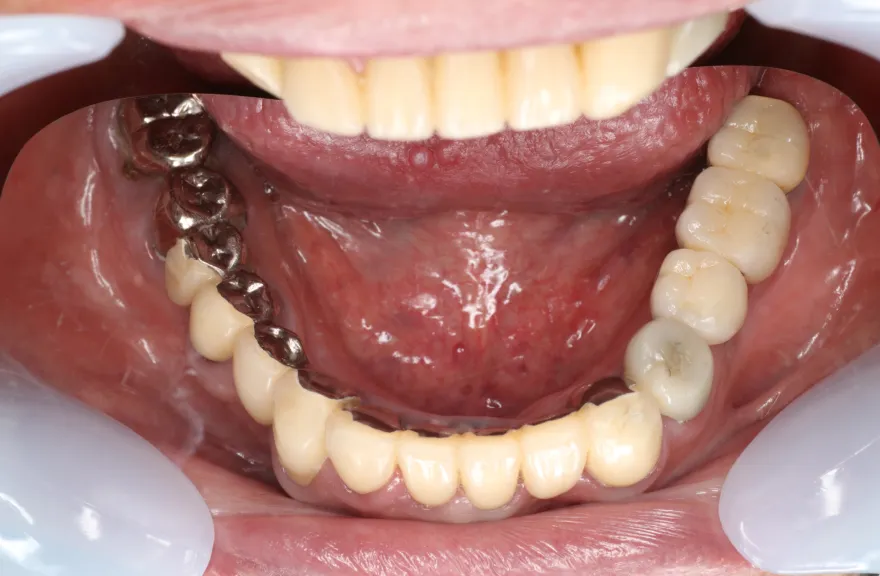

既にインプラント治療がなされており、使えるインプラントを使いながら足りないところにインプラントフィクスチャーを埋入し、噛み合わせを再構築する必要がある方でした。

上の前歯、右上の奥歯のインプラントはもう既に使える状態ではなく、また年月を経てすり減ってしまった下の前歯は噛み合わせを再構築する上で利用が難しい状況でした。

年齢を考えると、今回の治療で歯科治療を終えてしまい、残りの人生においてはメンテナンスのみで歯科へ通う状況を作りきってしまうことが求められました。

以上より、潔く残っている歯牙は抜去させていただき、上下をインプラントフィクスチャーによって固定式の歯を入れることとしました。 - 治療のリスク

レントゲンをよく見るとお分かりいただけるかと思いますが右下の奥歯のインプラント(レントゲンでは左右逆にうつるので、左下)が既にインプラント周囲炎になっていました。

本当に治療をやり切ってしまうなら、右下の奥2本のインプラントを抜去、新しいインプラントフィクスチャーを埋入すべき症例でした。

しかし、患者さんとの話し合いで、「まだ使えるインプラントは置いておこう」ということになり、右下のインプラントは置いたまま治療を行っています。今後の人生の中で腫れたり痛む可能性があることは重々ご承知いただいております。

複数のインプラントフィクスチャーの埋入においては埋入位置がずれると後々のクラウン製作に難が生じます。そのリスクを最低限にするため、ガイデッドサージェリーを行っております。